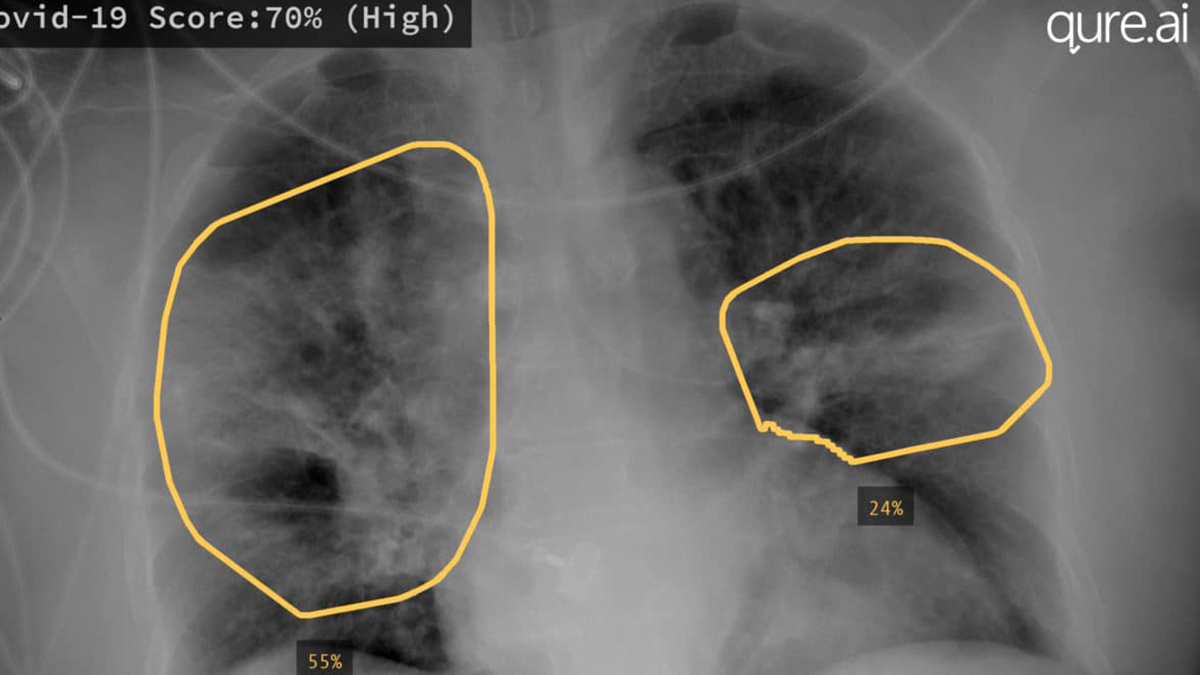

Medical Imaging Augmented With Ai Nvidia